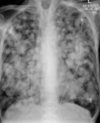

¿Qué distribución tiene la lx?

"Alas de mariposa"

Distribución en "alas de mariposa" se asocia a:

Influenza | O edema pulmonar alveolar